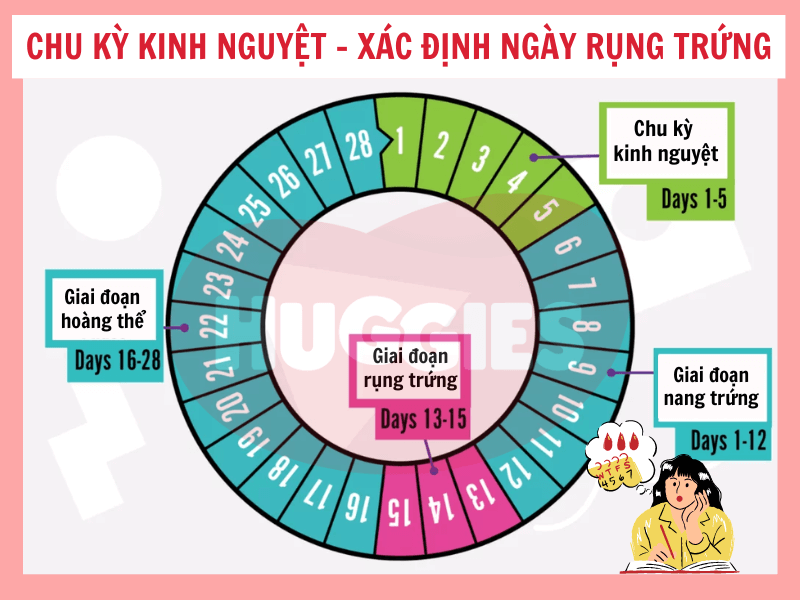

- Tin vào “tính ngày an toàn” nhưng chưa hiểu rõ cơ chế rụng trứng

- Tính ngày rụng trứng: Cần theo dõi chu kỳ kỹ lưỡng và không phù hợp với người có chu kỳ không đều.

Chào bạn thân mến, bạn có bao giờ tự hỏi làm thế nào để tính thời gian rụng trứng một cách chính xác nhất không? Việc hiểu rõ chu kỳ rụng trứng của bản thân không chỉ là kiến thức quan trọng về sức khỏe giới tính, mà còn là một cách tuyệt vời để […]

Chào bạn yêu quý, chúng ta lại gặp nhau rồi. Hôm nay, chúng ta sẽ cùng nhau trò chuyện về một chủ đề rất được quan tâm, đặc biệt là với những ai đang mong muốn chào đón một thành viên mới trong gia đình: đó là cách tính ngày rụng trứng thụ thai. Hiểu […]

Chào bạn thân mến, Tại Chuyenseg, chúng mình hiểu rằng hành trình khám phá và làm chủ cơ thể mình là một điều vô cùng thú vị và quan trọng. Đặc biệt, việc tính ngày rụng trứng chính xác là một trong những kiến thức nền tảng giúp bạn hiểu sâu hơn về chu kỳ […]